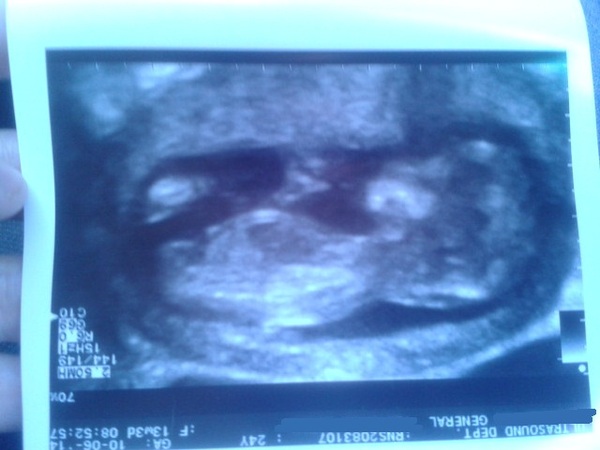

Scan was amazing. Super wiggly dancing baby,that wasn't impressed at being prodded with the scanner! Imaging was ace, could see hands, legs, face, allsorts :) Think it's got a bad lot as both dh and I have a big noses, baby will be no different ;)

Can see babies hands in this one - in the above one hands are both together clapping at the top! :) Baby started off facing my spine but rolled over halfway through Grin

I get so excited seeing everyone's scan pictures. Such a nice clear one there, Sasseh. I'm feeling both nervous and excited for mine on Thursday.